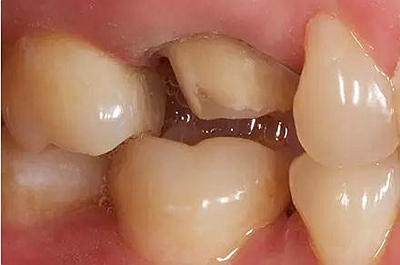

步骤4

咬合间距

与对牙合牙的咬牙合面间隙至少保留: 1.0 mm 点隙裂沟处的距离,1.5 mm 牙尖高度的距离。